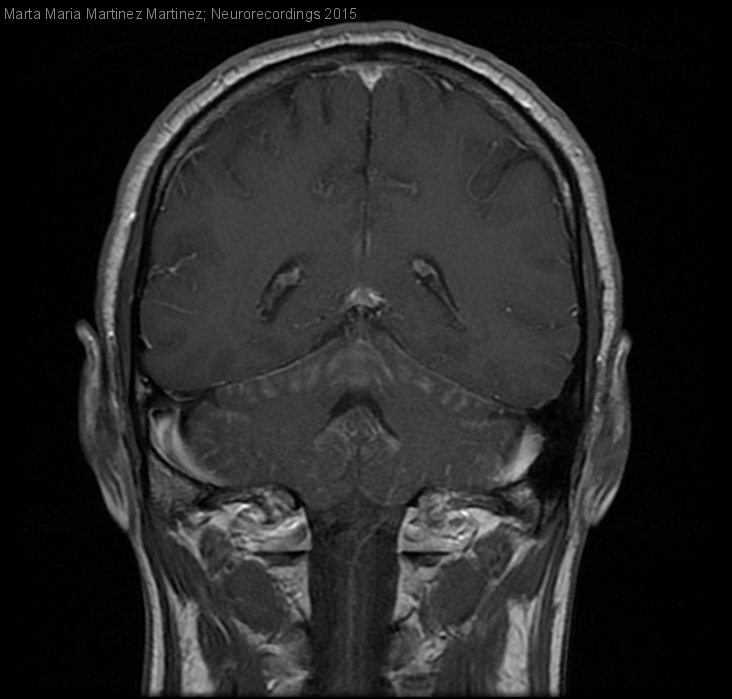

Diagnóstico final: CArcinomatosis meningea por posible carcinoma gástrico

Hombre | 54 años